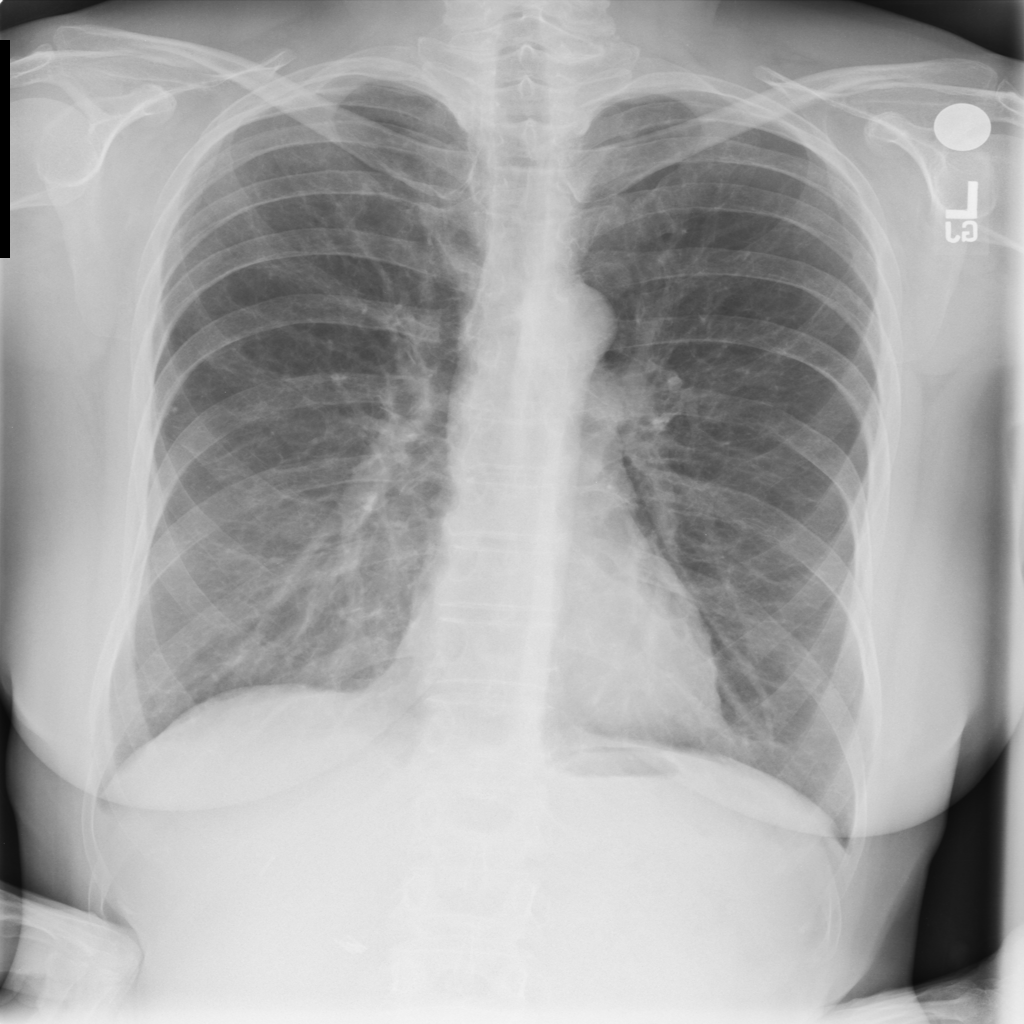

Consolidation

Consolidation refers to air-space filling that makes part of the lung appear denser on imaging.

Showing up to 90 reference images for Consolidation.

PAT-C1A7 · IMG-004Consolidation

PAT-C1A7 · IMG-004

PA